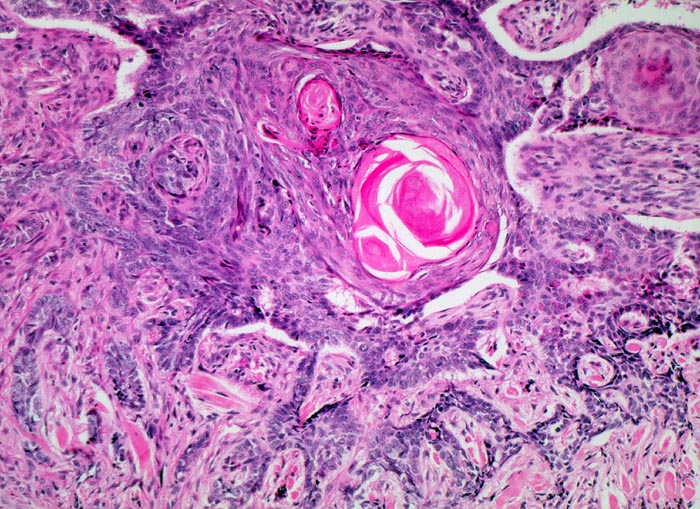

PathoPic ID 3951 - solides Basalzellkarzinom mit Verhornung

solides Basalzellkarzinom mit Verhornung

Zackig begrenzte Epithelverbände aus basaloiden Zellen mit randständiger Palisadierung. Hornperlen im Zentrum der grössten Epithelverbände.

Stark ulzerierender Wangentumor links